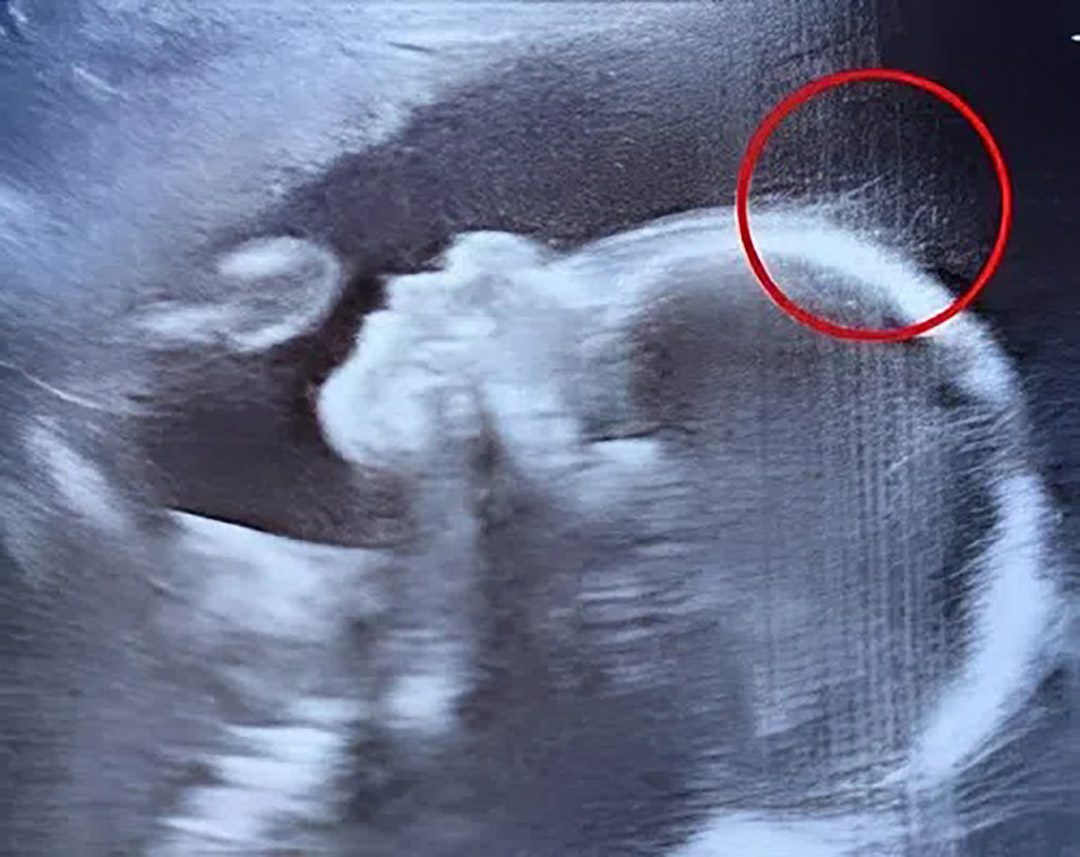

Une chevelure déjà visible à l’échographie : le début d’une histoire extraordinaire

Lors de son examen de routine, une future maman découvre avec stupéfaction que son bébé présente déjà une particularité visible à l'échographie. Ce détail apparemment anodin annonçait une naissance qui allait émerveiller son entourage et bien au-delà.